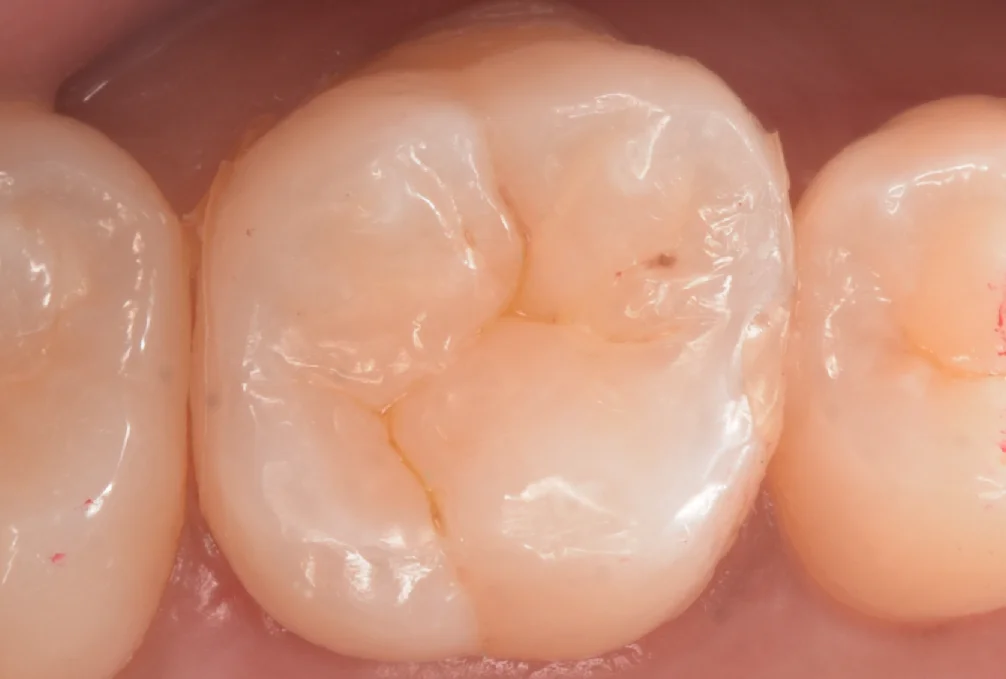

詰め終わって諸々の調整が終わったのがこちらになります。

シンプルな形態ではありますが、実は非常に難易度の高い歯の形でした。

見る人が見るとわかるというやつです(笑)

術前術後です。

違和感なく綺麗に仕上げられたかと思います。

歯の前後の部分に接着剤のバリが残っていますが、処理をしたわけではないので、歯ブラシや食事で普通に外れてくれます。

・・・もし次回残ってたらちゃんと除去しますね(⌒-⌒; )